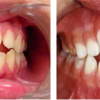

Diasteem – vahe esimeste hammaste vahel. Esineb 50%-l 6-8 aastastel lastel. Kuni 2 mm diasteemi puhul on, peale lateraalse intsisiivi ja silmahamba lõikumist, võimalik diasteemi iseeneslik sulgumine. Diasteem, mille suurus...